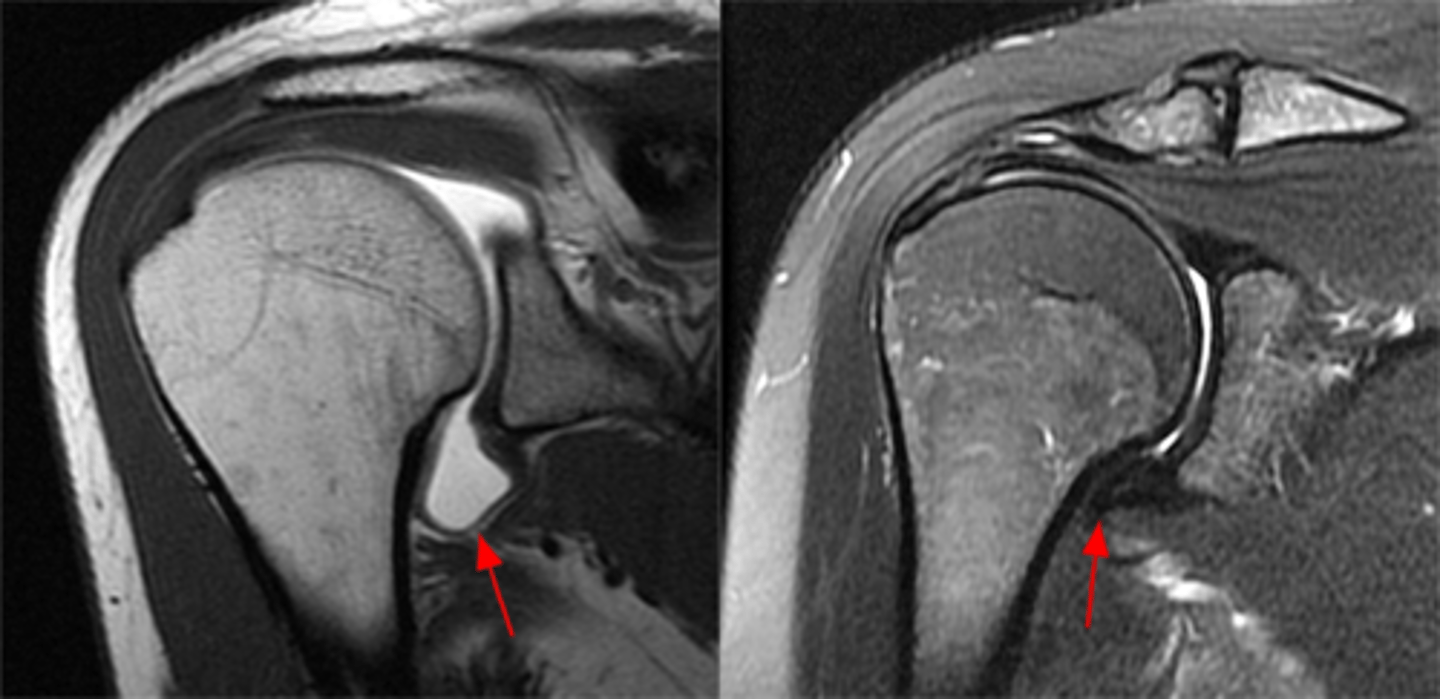

Complete thickness tear of the supraspinatus w/ major bucking and retraction as the muscle pulls the tendon back

What are these images depicting w/ the rotator cuff?